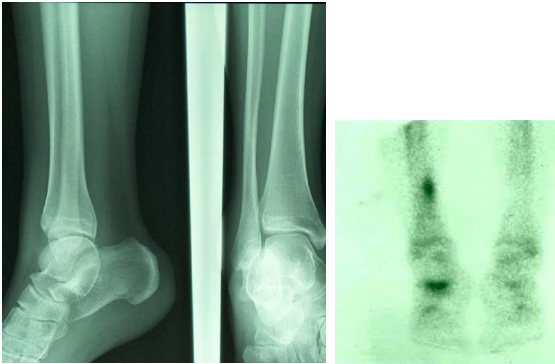

Bone scan

Principles, Indications, and Examples

Principles and indications

Detection, staging and follow-up of bone metastasis

Differentiating between osteomyelitis and cellulitis

Determination of bone viability

Evaluation of difficult fracture (stress fracture, fracture in battered child)

Evaluation of prosthetic joint problems (loosening, infected prosthesis)

Evaluation of bone pain in patient with normal plain radiograph (unexplained bone pain) Radiotracer: 99mTc-MDP (methylene diphosphonate)

Pathophysiology

Chemisorption to the hydroxyapatite crystal

Increased uptake

Increased blood flow

Increased osteoid formation

Increased mineralization of osteoid

Interrupted sympathetic nerve supply